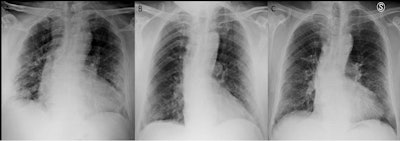

Chest x-rays performed three months after patients with COVID-19 are discharged from hospital can identify those who might need additional follow-up treatment, according to a study published October 22 in Radiography.

Italian researchers analyzed chest x-rays of COVID-19 patients acquired at admission, prior to discharge, and three months later and found abnormalities were present in about half of patients. Based on a scoring system the authors used, the finding could help prioritize patients with more severe clinical and radiological findings, the authors wrote.

Two radiologists evaluated the chest x-rays of patients at admission, at discharge, and at three months using an 18-point scoring system. The scoring system divided lungs into three equal parts: upper, middle, and lower, for a total of six zones. Scores from 0 to 3 were assigned to each zone based on lung abnormalities detected on a frontal view, as follows:

- 0 -- No abnormalities

- 1 -- Interstitial infiltrates; defined as septal thickenings and focal or extensive opacity, with the evidence of extravascular structure

- 2 -- Interstitial and alveolar infiltrates (interstitial predominance)

- 3 -- Interstitial and alveolar infiltrates (alveolar predominance)

The single scores of the six lung zones in each patient were added to obtain an overall chest x-ray score ranging from 0 to 18. Patients were divided into groups with scores of 0 or scores ≥ 1, and clinical-radiological findings were compared between them.

About half of patients (49.6%) had chest x-ray scores of 0, which indicated a complete radiological recovery three months after discharge. The other half (50.4%) had x-ray scores of 3 (+/- 2.6) at three months. In patients with higher scores at three months, age, the number of days of hospitalization and their chest x-ray scores at admission and before discharge were also statistically higher, the researchers found.

"Radiological abnormalities persist three months after discharge in a high proportion of COVID-19 patients," the authors wrote.

Ultimately, the study suggests that evaluating chest x-rays scores at admission and before COVID-19 patients are discharged can identify those who may benefit from a closer follow-up and targeted management, the researchers concluded.